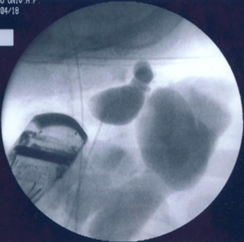

診断には、視診の他、超音波検査やCT検査、MRI検査などの画像検査を組み合わせて行います。画像検査上の病変の見え方の違いから、嚢胞状や海綿状、その混合型などに分類されます。治療は、”完全切除”できる病変に対して外科手術も選択肢の一つになりますが、病変内への薬剤の注入による硬化療法が広く行われています。硬化療法の原理は、病変内に注入された薬剤が嚢胞性病変内で炎症反応を起こすことで嚢胞壁が癒着することで嚢胞が潰れて、リンパ管腫が腫れなくなるというものです。当院では、薬剤の注入時に病変内で薬剤の広がり具合をリアルタイムに確認するために血管造影に用いる造影剤を薬剤に混ぜて、硬化療法を行っています。造影剤を併用することにより大きく広がった病変や超音波検査で追跡できない深部病変への薬剤の広がりをリアルタイムに確認し、その治療効果の判定や今後の治療方針に役立てることができると考えています。

頚部リンパ管腫に対して硬化治療が奏功した一例

胎児超音波検査で頚部リンパ管腫を指摘されていた症例で、生後4か月時に病変が急速に増大して、呼吸困難で受診、外来で緊急気管挿管・緊急入院となりましたが、透視下に硬化療法を行ったところ、嚢胞性病変のほとんどが潰れて、治療後は腫れなくなり、元気に過ごしています。

圧迫して呼吸促迫になったため緊急気管挿管

(左頚部から縦隔に広がる病変)

病変内に注入し、透視で病変への広がりを

リアルタイムに確認。CT画像で指摘された

病変に一致して薬剤が広がった。

頚部の腫瘤はほとんど目立たなくなった。